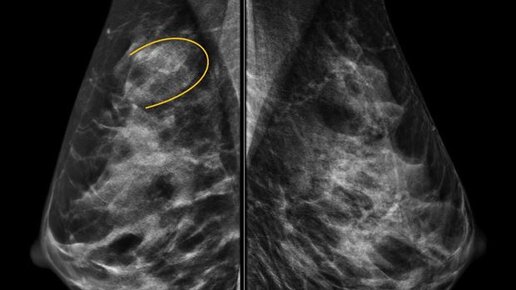

Скрупулезная диагностика и своевременное лечение РМЖ

Маммология является узкой специальностью, требующей большого опыта и знаний. Большое количество различных методов исследования, широкий спектр клинических симптомов и вариантов строения молочной железы – все это обуславливает необходимость внимательного и индивидуального подхода в каждом конкретном случае. Врачи Ильинской больницы - мультимодальные специалисты с большим опытом работы. Мы регулярно работаем со сложными диагностическими случаями, выполняем высокотехнологические исследования и вмешательства...